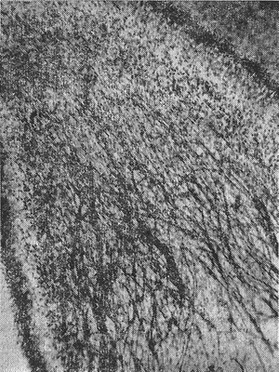

![]() Рис. 3. Пучки нервових волокон, що розгалужуються в центральних відділах пульпи першого премоляра дитини 12 років. Коріння сформовані на 2/3. Про. 8, ок. 10 (А. Д. Джафаровой, 1969). |

Іннервації постійних зубів з повністю сформованими коренями присвячені дослідження багатьох авторів. Що ж стосується стану иннервационного апарату постійних зубів на різних стадіях їх розвитку, починаючи з моменту прорізування, то це питання не знайшов відображення в літературі. Перші роботи в цьому напрямку належать А. Д. Джафаровой (1969). Її дослідження показали, що в період прорізування зубів і формування коренів на 1/3-1/2 в пульпі виявляються лише окремі нервові волокна (рис. 2). Вони добре виявляються в області рогів. Однак пододонтобластное сплетіння до цього часу ще не виражене. По мірі розвитку зуба кількість нервових волокон збільшується. Так, у зубах, коріння яких сформовані на 2/3, в центральних відділах пульпи постійно виявляються пучки нервових волокон, які, розгалужуючись, направляються до рогів пульпи. Зростає кількість термінальних розгалужень, а під шаром одонтобластів зазначається освіта нервового сплетення, найбільш добре вираженого в області рогів. Збільшується кількість м'якушевих волокон, які визначаються як в центральних відділах пульпи, так і в області рогів (рис. 3). Збільшується і кількість нервових рецепторів.